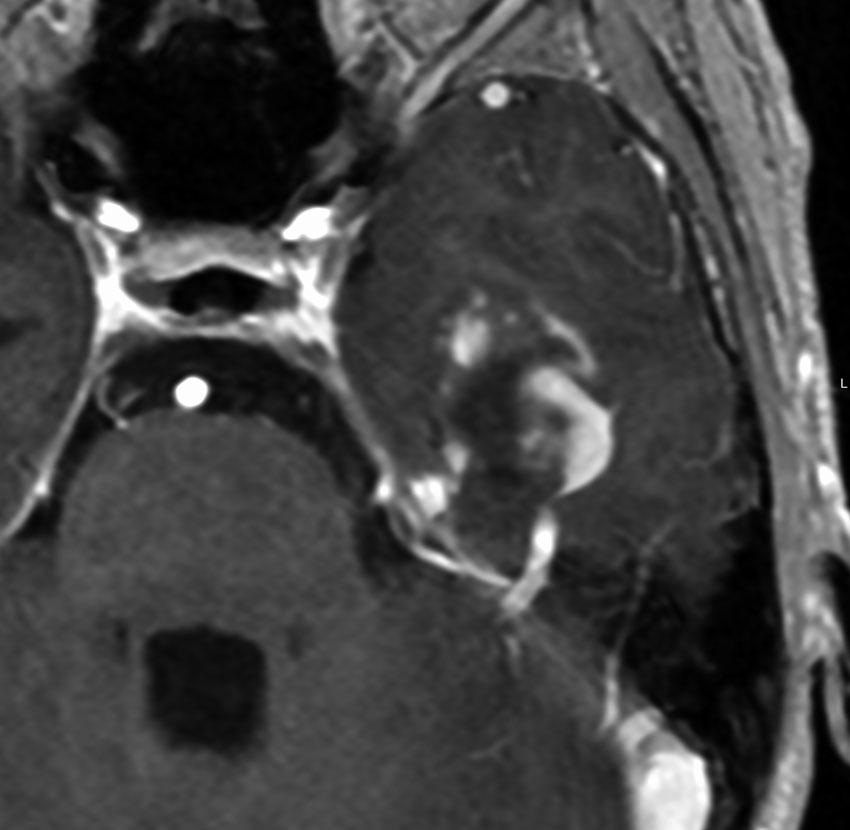

神経線維腫症1型に合併した退形成を示す anaplastic PXA

もともと停止性水頭症があり経過観察を受けていたNF-1の患者さんに発生したものです。嘔気と左片麻痺で発症しました。 開頭手術で亜全摘出(ほぼ全摘)しました。

術後に小さな腫瘍が残っていた(左の画像)ので54Gy/27frの放射線治療をしましたが,無効でした。結局,再開頭手術で残存腫瘍を摘出しました。3年後に同じ部位で再発(中央の画像)したので,また開頭手術で摘出しました。そのまた3年後に同じ部位で再発しました(右側の画像)。この様に,摘出しきれなければ治らないし,摘出できれば治る可能性の高い腫瘍です。腫瘍床での再発は多いものの,転移とか脳深部への浸潤性増殖は少ないといえる腫瘍です。放射線治療が効きにくいということを併せて,atypical meningioma WHO grade 2と似た性格を有しています。